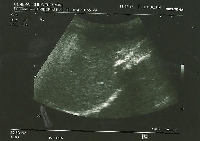

Πρόκειται για γυναίκα ασθενή 55 ετών η οποία είχε υποβληθεί σε σιγμοειδεκτομή και μετεγχειρητική χημειοθεραπεία για αδενοκαρκίνωμα του παχέος εντέρου (Τ3Ν1). Ένα έτος μετά τη σιγμοειδεκτομή, κατά τον τακτικό απεικονιστικό έλεγχο (MDCT), αναγνωρίστηκε μονήρης μεταστατική εστία στη μετάπτωση των ηπατικών τμημάτων 3 & 4b. Υποβλήθηκε εκ νέου σε χημειοθεραπεία (neoadjuvant) 6 κύκλων. Το διεγχειρητικό υπερηχογράφημα δεν ανέδειξε άλλες, πλην της ήδη γνωστής, ηπατικές μεταστάσεις (εικόνα 1). Ύστερα από ηπατική κινητοποίηση (εικόνα 2), υποβλήθηκε σε αριστερή ηπατεκτομή (εικόνες 3 & 4), με διατήρηση του κερκοφόρου λοβού (κλάδος PV1). Το ηπατικό υπόλειμμα φαίνεται στην εικόνα 5. Η ασθενής έλαβε εξιτήριο την 6η μετεγχειρητική ημέρα. Η χημειοθεραπεία (adjuvant) θα ολοκληρωθεί με άλλους 6 κύκλους.